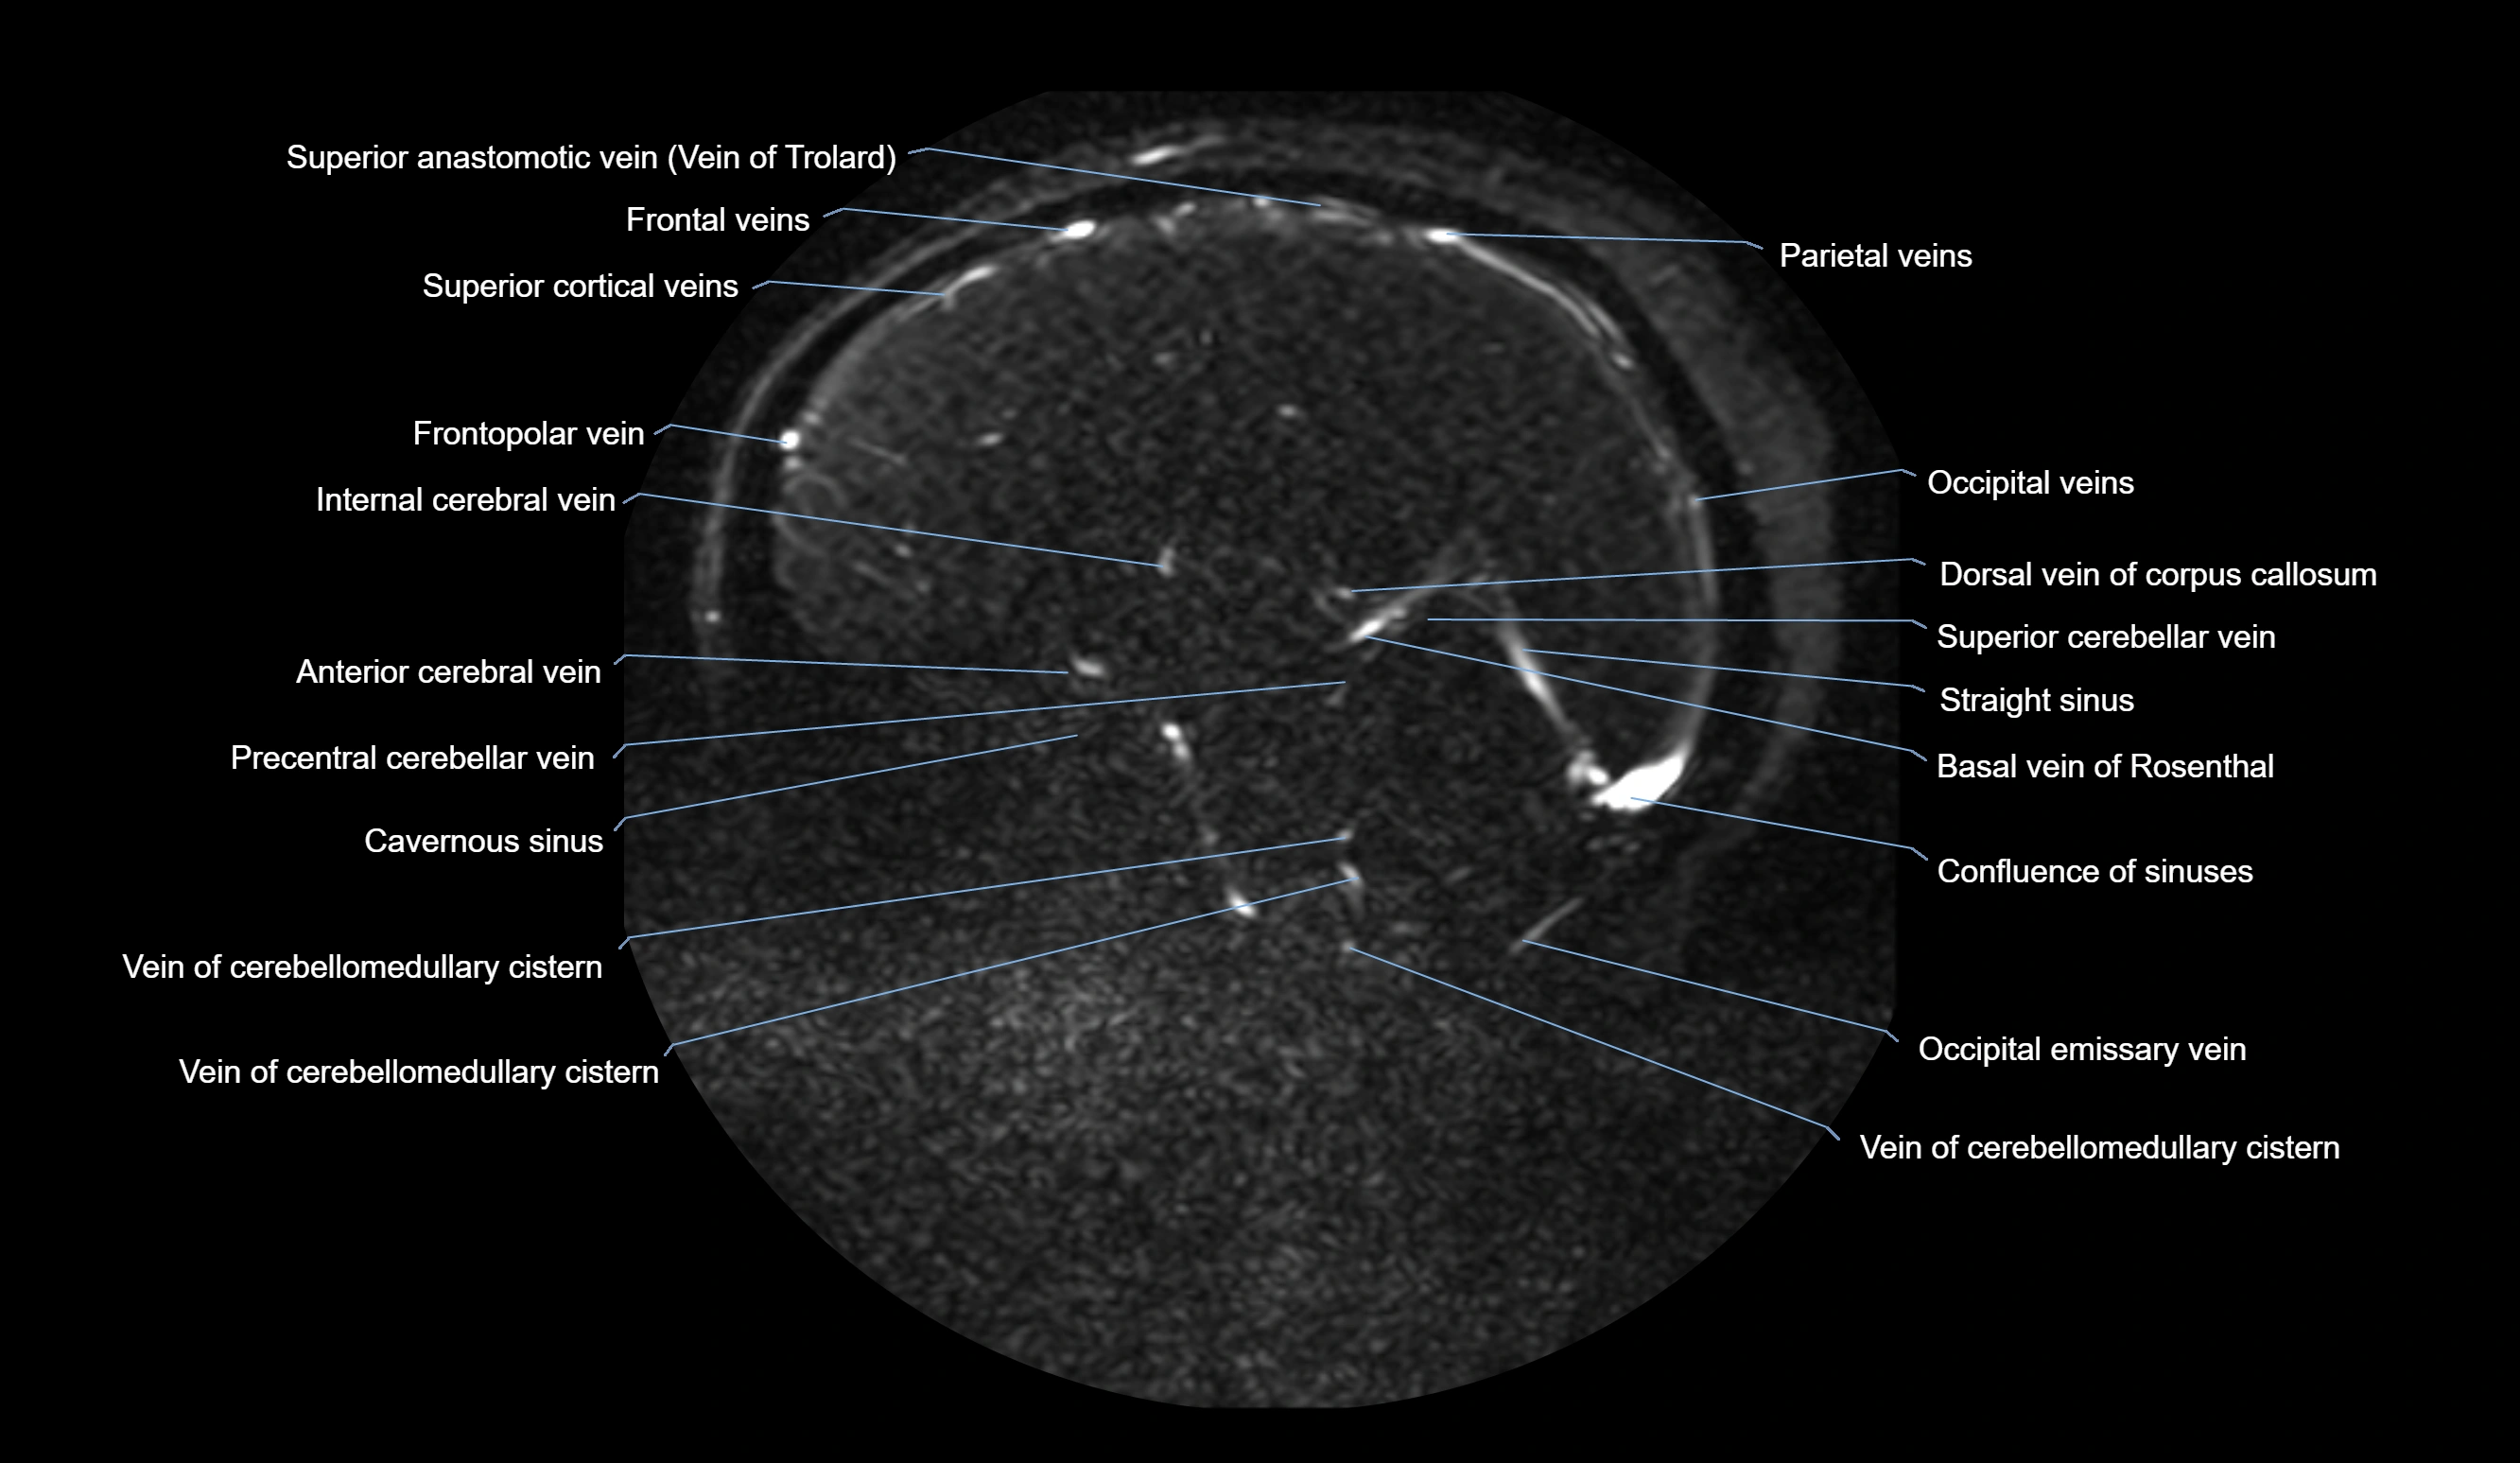

MRI images

image